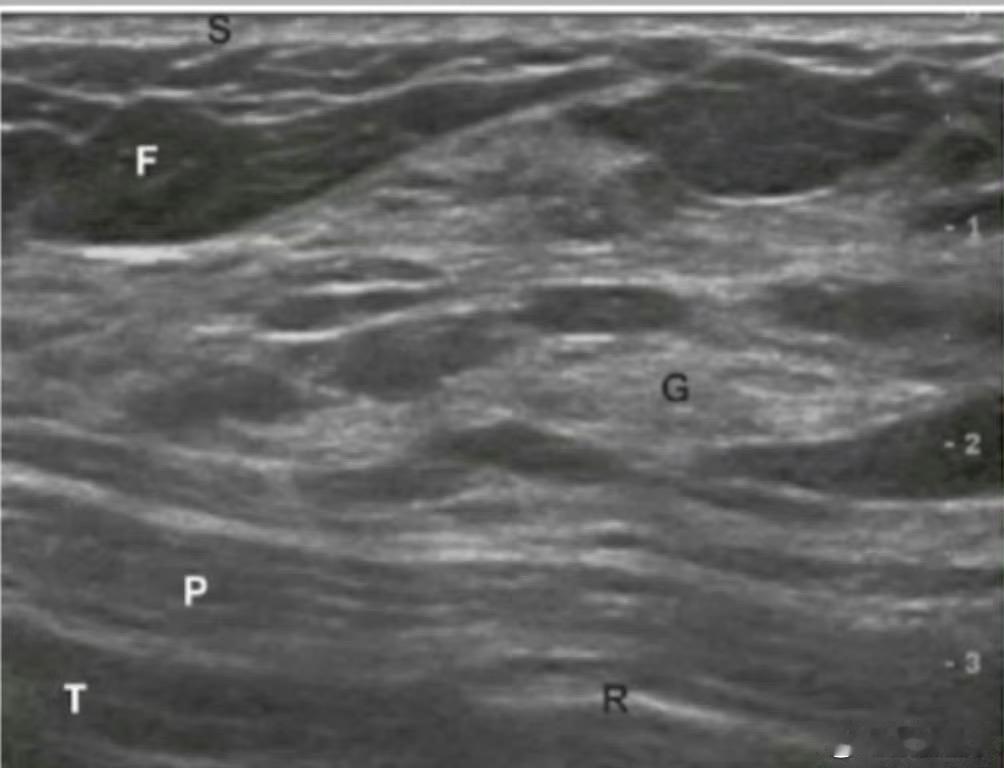

只有在合适的时间进行乳房B超检查,才可以清晰地显示从皮肤表面到胸壁的乳腺解剖结构[4]。

正常乳房的超声影像,显示乳腺解剖结构[4]